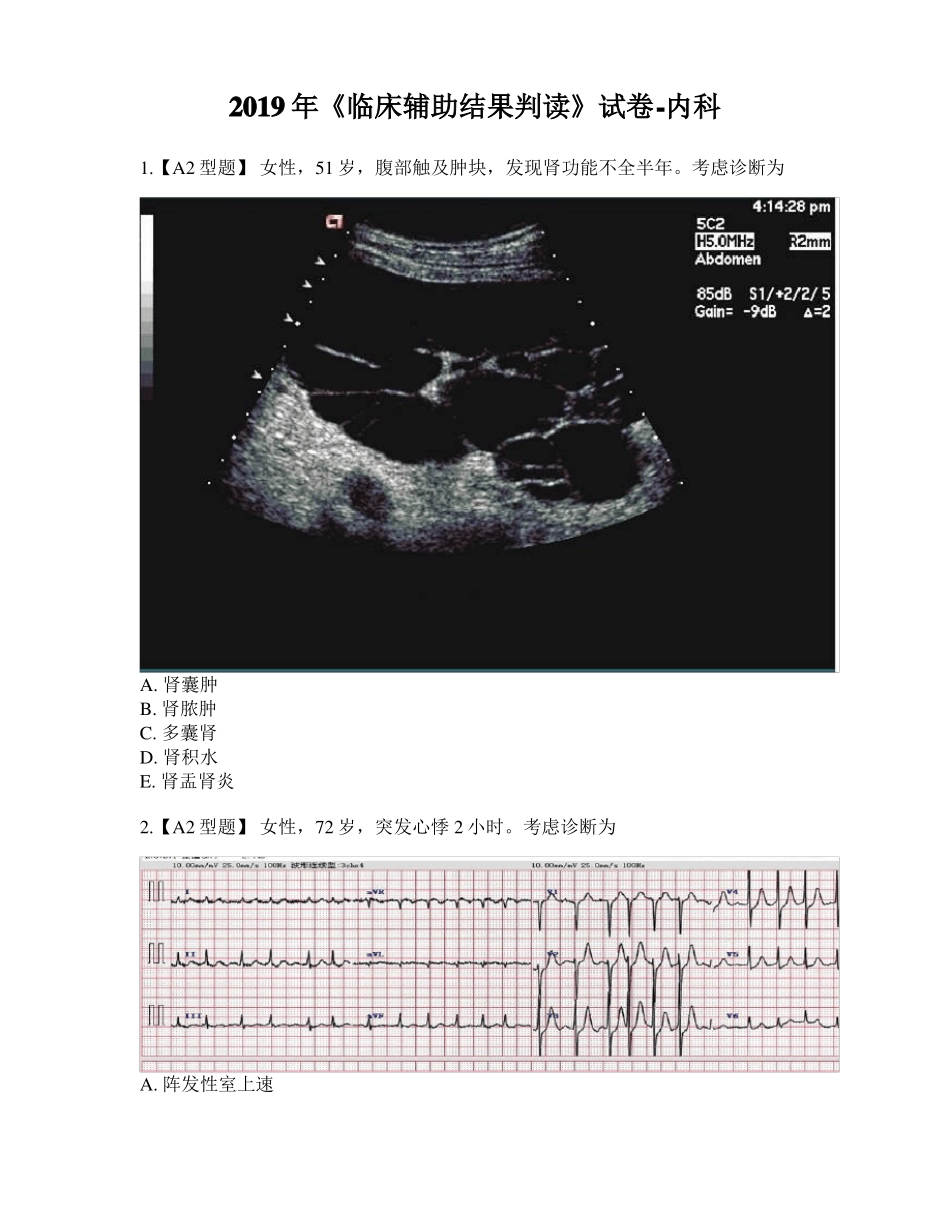

2019 年《临床辅助结果判读》试卷-内科1.【A2 型题】 女性,51 岁,腹部触及肿块,发现肾功能不全半年。考虑诊断为A. 肾囊肿B. 肾脓肿C. 多囊肾D. 肾积水E. 肾盂肾炎2.【A2 型题】 女性,72 岁,突发心悸 2 小时。考虑诊断为A. 阵发性室上速B. 房扑C. 室速D. 房颤E. 窦性心动过速3.【A2 型题】 男性,21 岁,腰部绞痛伴肉眼血尿 3 小时。考虑诊断为A. 输尿管结石B. 肾结石C. 膀胱结石D. 肠梗阻E. 肾积水4.【A2 型题】 一慢性肺心病患者,因呼吸困难伴双下肢浮肿住院,住院后经抗感染,强心,利尿以后双下肢浮肿减轻,但出现恶心,烦躁。血气结果示:pH7.41,PaCO2 9.67kPa(67mmHg),HCO3- 42mmol/L,血 Na+ 140mmol/L,Cl-90 mmol/L。结论为A. 代偿性呼吸性酸中毒B. 代偿性代谢性碱中毒C. 失代偿性呼吸性酸中毒D. 呼酸合并代碱E. 代偿性代谢性酸中毒5.【A2 型题】 男,50 岁,腹胀消瘦食欲减退二月余,有轻度黄染,既往有肝硬化病史,AFP 阳性。诊断为A. 肝硬变B. 肝癌C. 脂肪肝D. 肝脓肿E. 肝炎6.【A2 型题】 患者女性,45 岁咳嗽、发热 20 天,加重伴活动后气促 1 周。诊断为A. 右下肺炎B. 右下肺不张C. 右侧胸腔积液D. 右下肺癌伴肺不张E. 左下肺炎7.【A2 型题】 病史:女,66 岁,反复咳嗽、咳痰 20 年,呼吸困难、伴咯血 2天,诊断A. 肥厚型心肌病B. 风湿性心脏病二尖瓣狭窄C. 风湿性心脏病二尖瓣关闭不全D. 风湿性心脏病主动脉瓣狭窄E. 扩张型心肌病8.【A2 型题】 患者男,65 岁,以“左下腹痛伴便血 2 月”入院。肠镜提示距肛20CM 见一新生物,占据肠腔 1 周,内镜不能通过。诊断为A. 结肠溃疡B. 结肠平滑肌瘤C. 结肠癌D. 结肠息肉E. 慢性结肠炎9.【A2 型题】 患者男性,56 岁,主诉:咳嗽 2 月余。诊断为A. 右上浸润性结核B. 右上肺炎C. 右上周围型肺癌D. 左上肺结核球E. 左上肺炎10.【A2 型题】 患者男,67 岁,以“左上腹痛伴腰背部放射痛半年”入院。患者此次入院 B 超发现有“胰腺团块状回声改变,密度不均”。CA199 6844KU/L,该患者首先考虑的诊断为A. 急性胰腺炎B. 慢性胰腺炎C. 胰腺癌D. 胰腺脓肿E. 胰腺囊肿11.【A2 型题】 患者男性,59 岁,吸烟史 30 余年。乏力,咳嗽 1 月来院。查:血钠 120mmol/L。患者低钠最可能的原因是什么A. 甲亢B. 甲减C. 副癌综合征D. 肺炎E. 肺结核12.【A2 型题】 ...